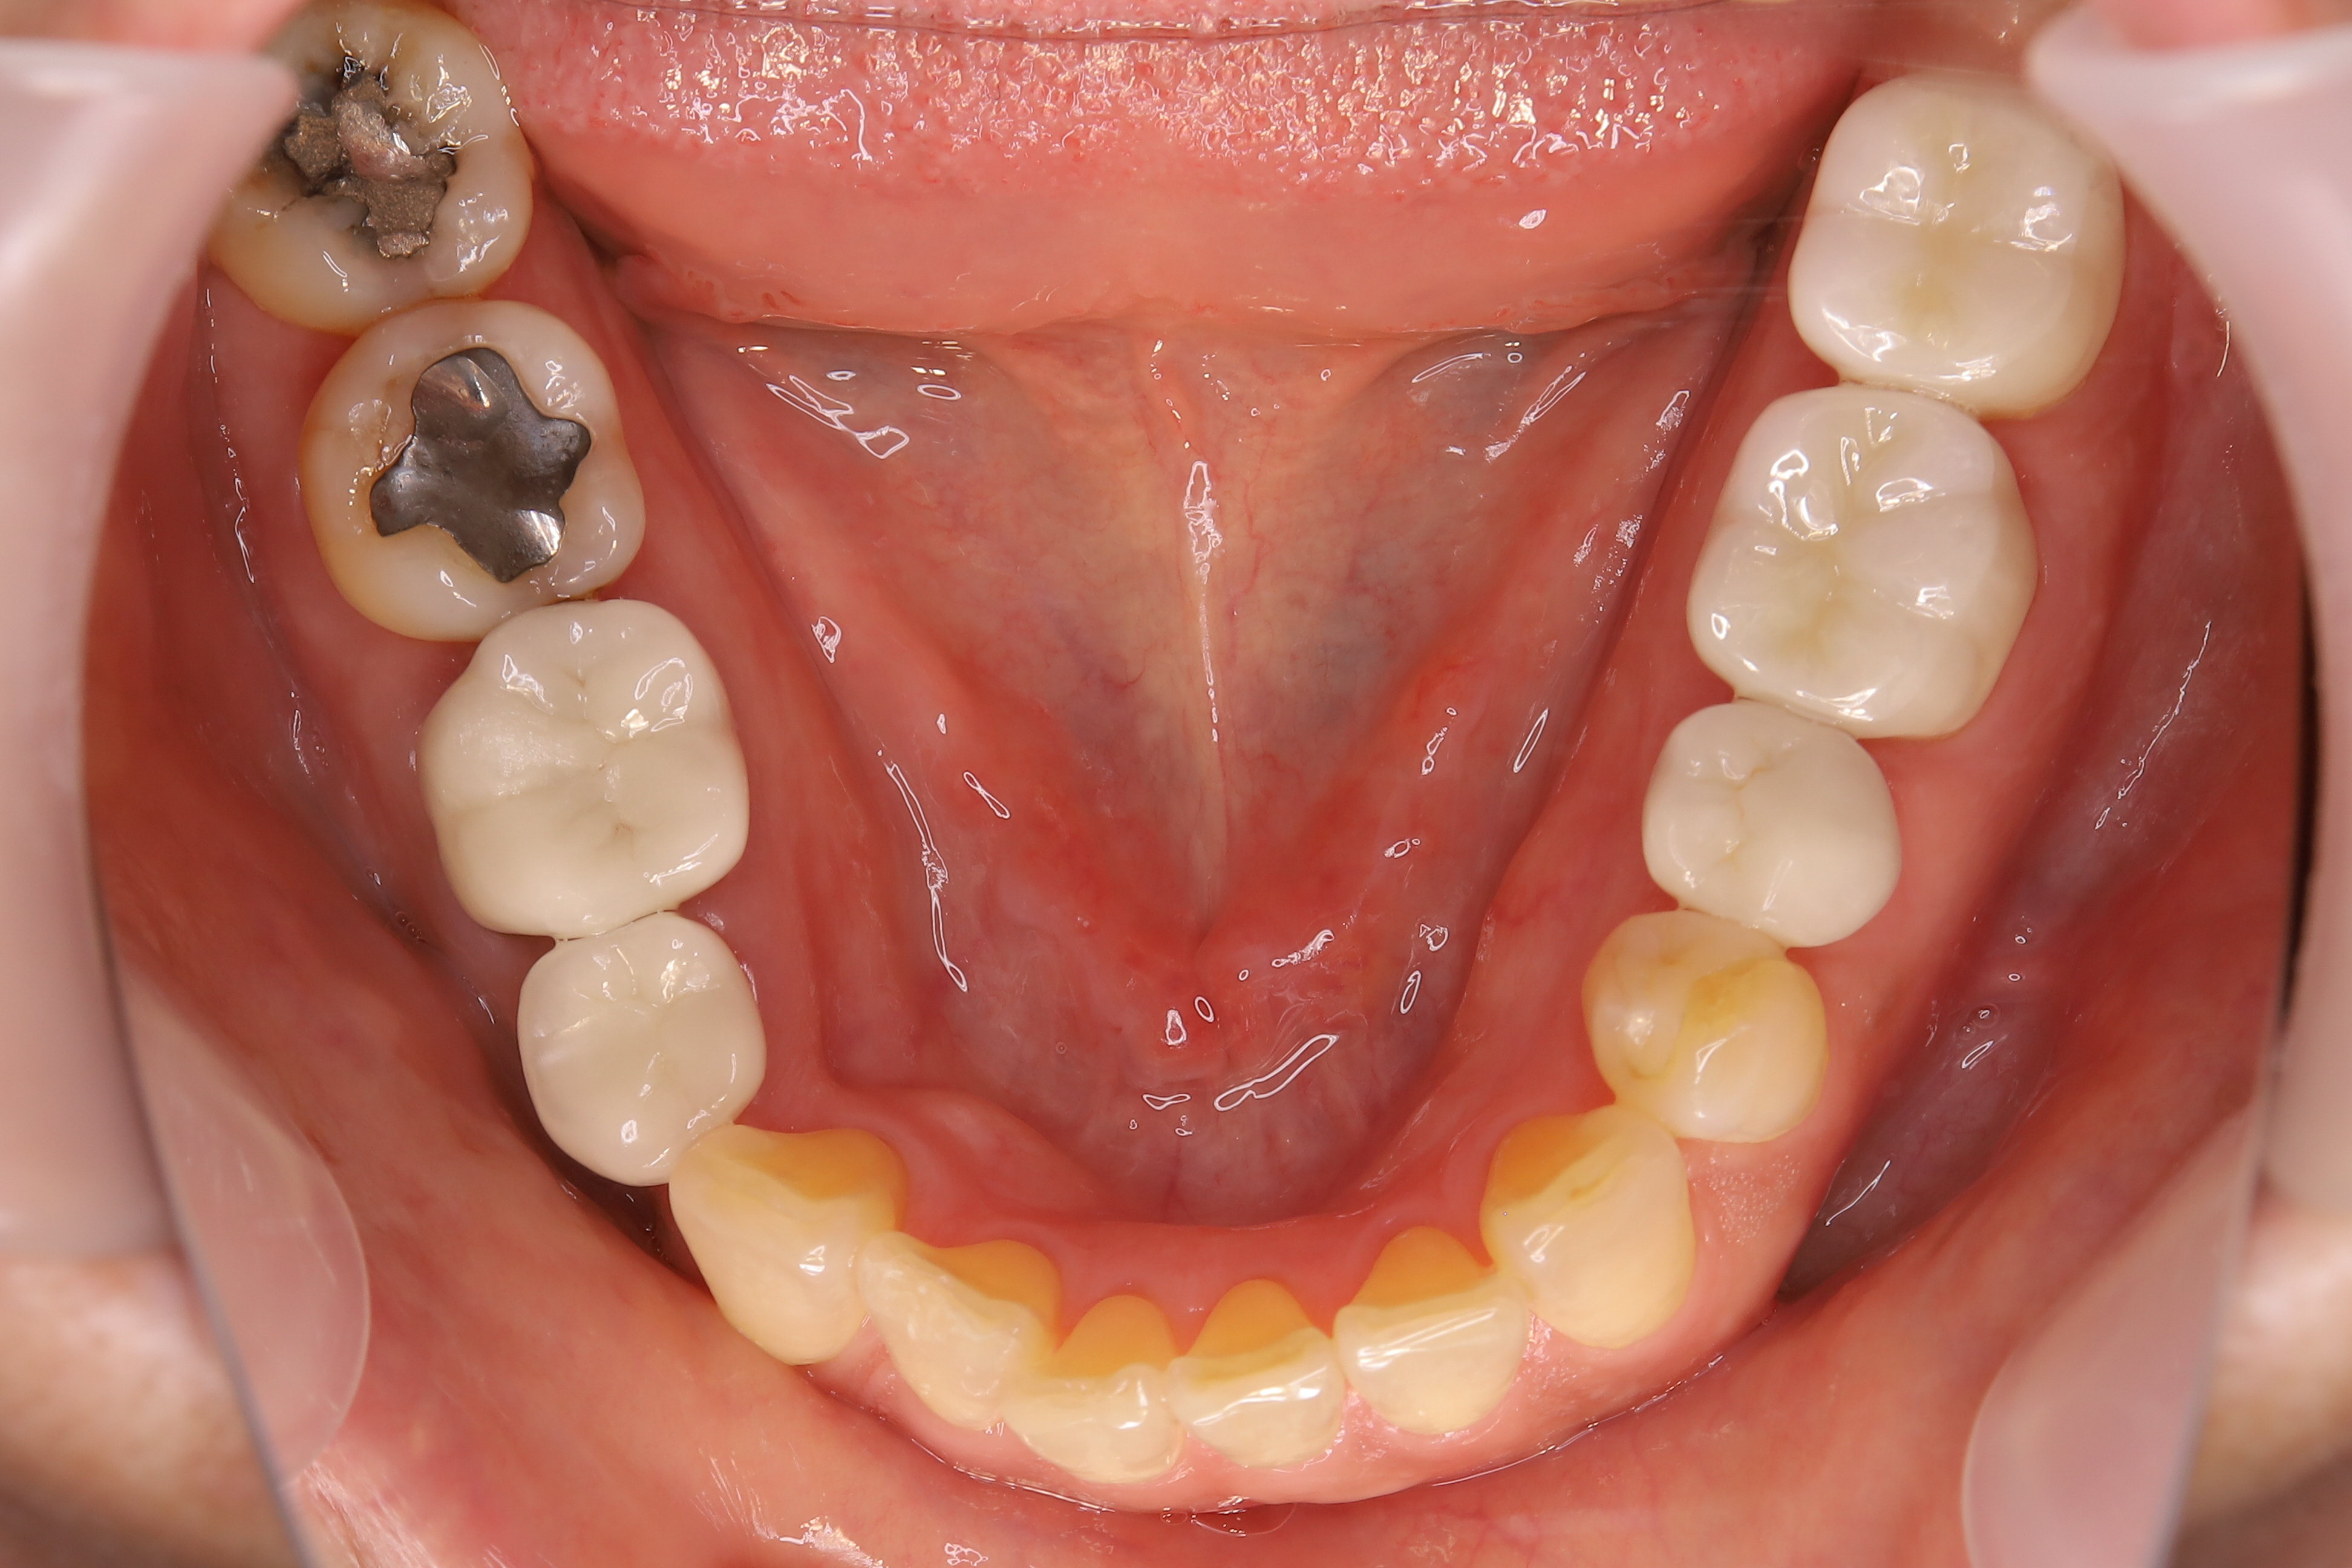

審美歯科治療

症例紹介